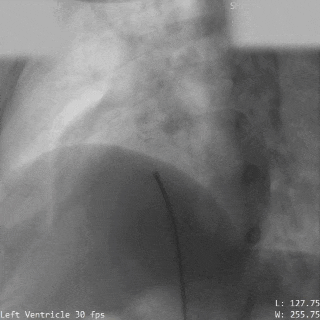

术前造影

主动脉瓣上造影,破口约5mm

释放前瓣上造影

分流明显减少